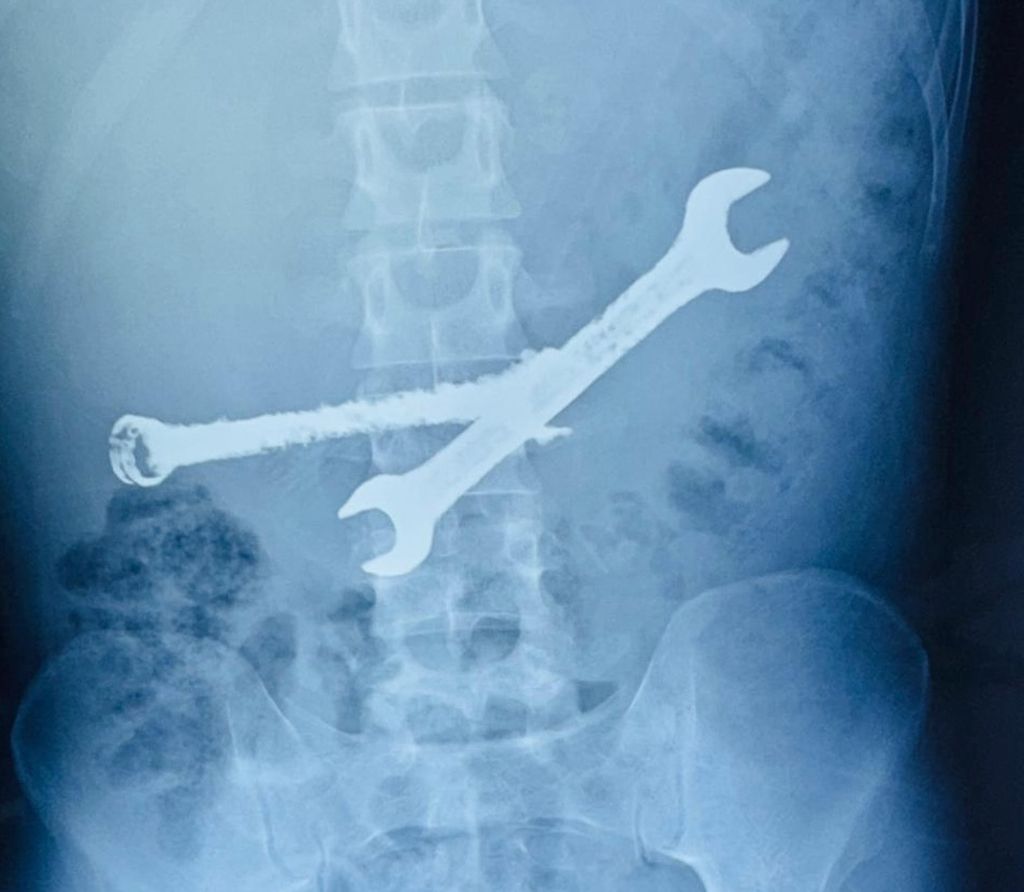

Liječnici koji su pregledavali njegov želudac pronašli su sedam četkica za zube i dva montažna ključa, koji su ondje bili tjednima. I nije bilo drugog načina da ih se izvadi osim operacije, koja je trajala više od dva sata.

Liječnici su muškarčev želudac nakon zahvata opisali kao "odlagalište smeća", a kažu kako je pravo čudo da je ostao živ.

Rekli su da je pacijent imao naviku gutati metalni alat i četkice za zube, što je navodno počeo raditi mjesec dana prije hospitalizacije.